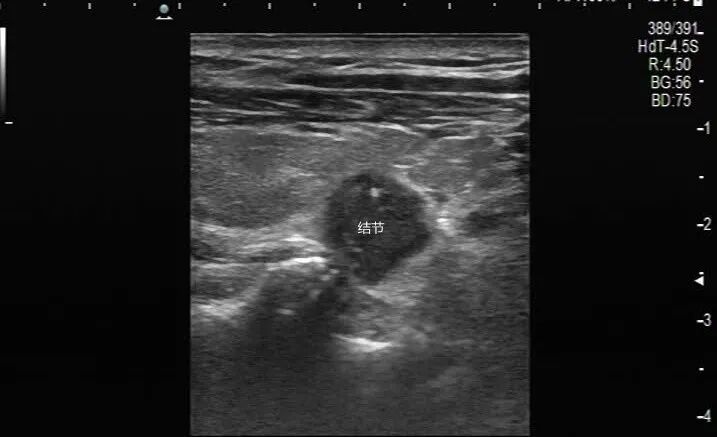

常規(guī)超聲評估:甲狀腺右葉見一個實(shí)性低回聲腫物,邊緣毛刺,縱橫比大于1,內(nèi)血流不豐富,甲狀腺分類妥妥的4類(以上是詞句是針對上幅圖的描述)